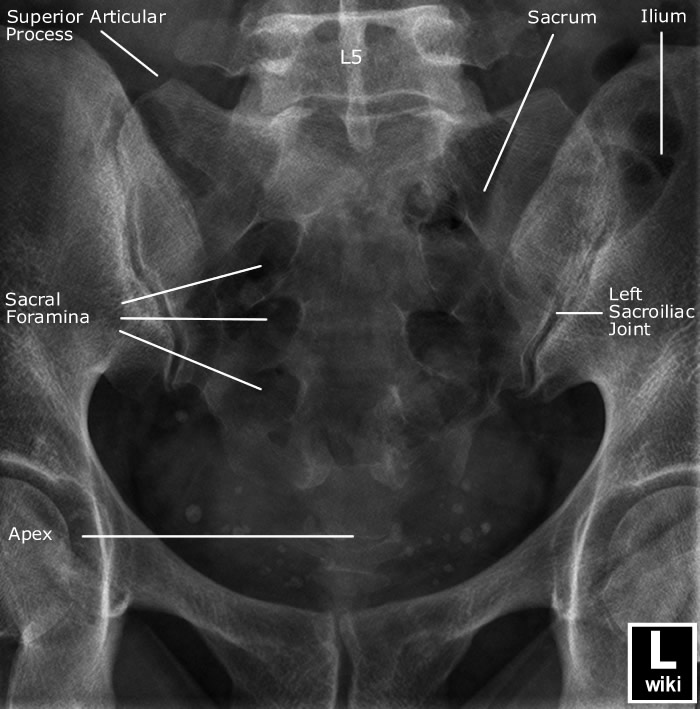

| AP view (Lumbar) | AP view (Sacrum) |

![]() |